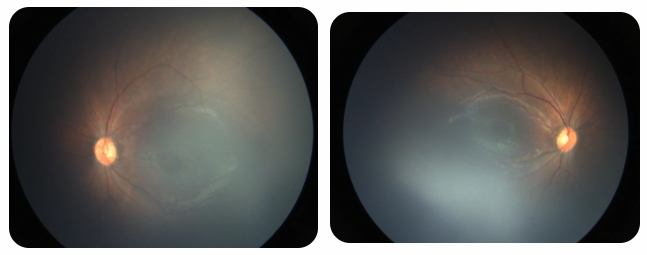

廈門眼科中心黎曉新名醫(yī)工作室曾接診一名31周出生的早產(chǎn)兒,出生體重僅1300克。由于家長(zhǎng)缺乏篩查意識(shí),直到孩子5個(gè)月大時(shí)眼睛仍不會(huì)追光,才前來(lái)就診。檢查發(fā)現(xiàn),患兒ROP已進(jìn)展至4B期,因纖維血管增殖牽拉導(dǎo)致視網(wǎng)膜脫離,錯(cuò)過了最佳治療窗口。盡管黎曉新教授團(tuán)隊(duì)成功實(shí)施了玻璃體切割手術(shù),孩子的視力仍存在不可逆損傷。此后,孩子開啟了長(zhǎng)期隨診復(fù)查、治療的“護(hù)眼征程”,目前其右眼矯正視力為0.6,左眼為0.8。

近期術(shù)前檢查:

早產(chǎn)兒視網(wǎng)膜病變

術(shù)后復(fù)查:

相比之下,另一位早產(chǎn)寶寶在出生5周后,生命體征穩(wěn)定之時(shí),便在產(chǎn)科醫(yī)生的建議下轉(zhuǎn)診至廈門眼科中心。經(jīng)篩查確診為Ⅲ期ROP,黎曉新教授團(tuán)隊(duì)及時(shí)為其進(jìn)行了激光治療。半年后復(fù)查顯示,寶寶的視網(wǎng)膜血管發(fā)育正常,視力發(fā)育與足月兒童無(wú)異。